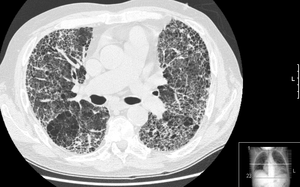

HRCT of lung showing extensive fibrosis possibly from usual interstitial pneumonitis. There is also a large emphysematous bulla.

- إختبارات التصوير:

• الأشعة السينية X-RAY.

• الأشعة المقطعية CT.